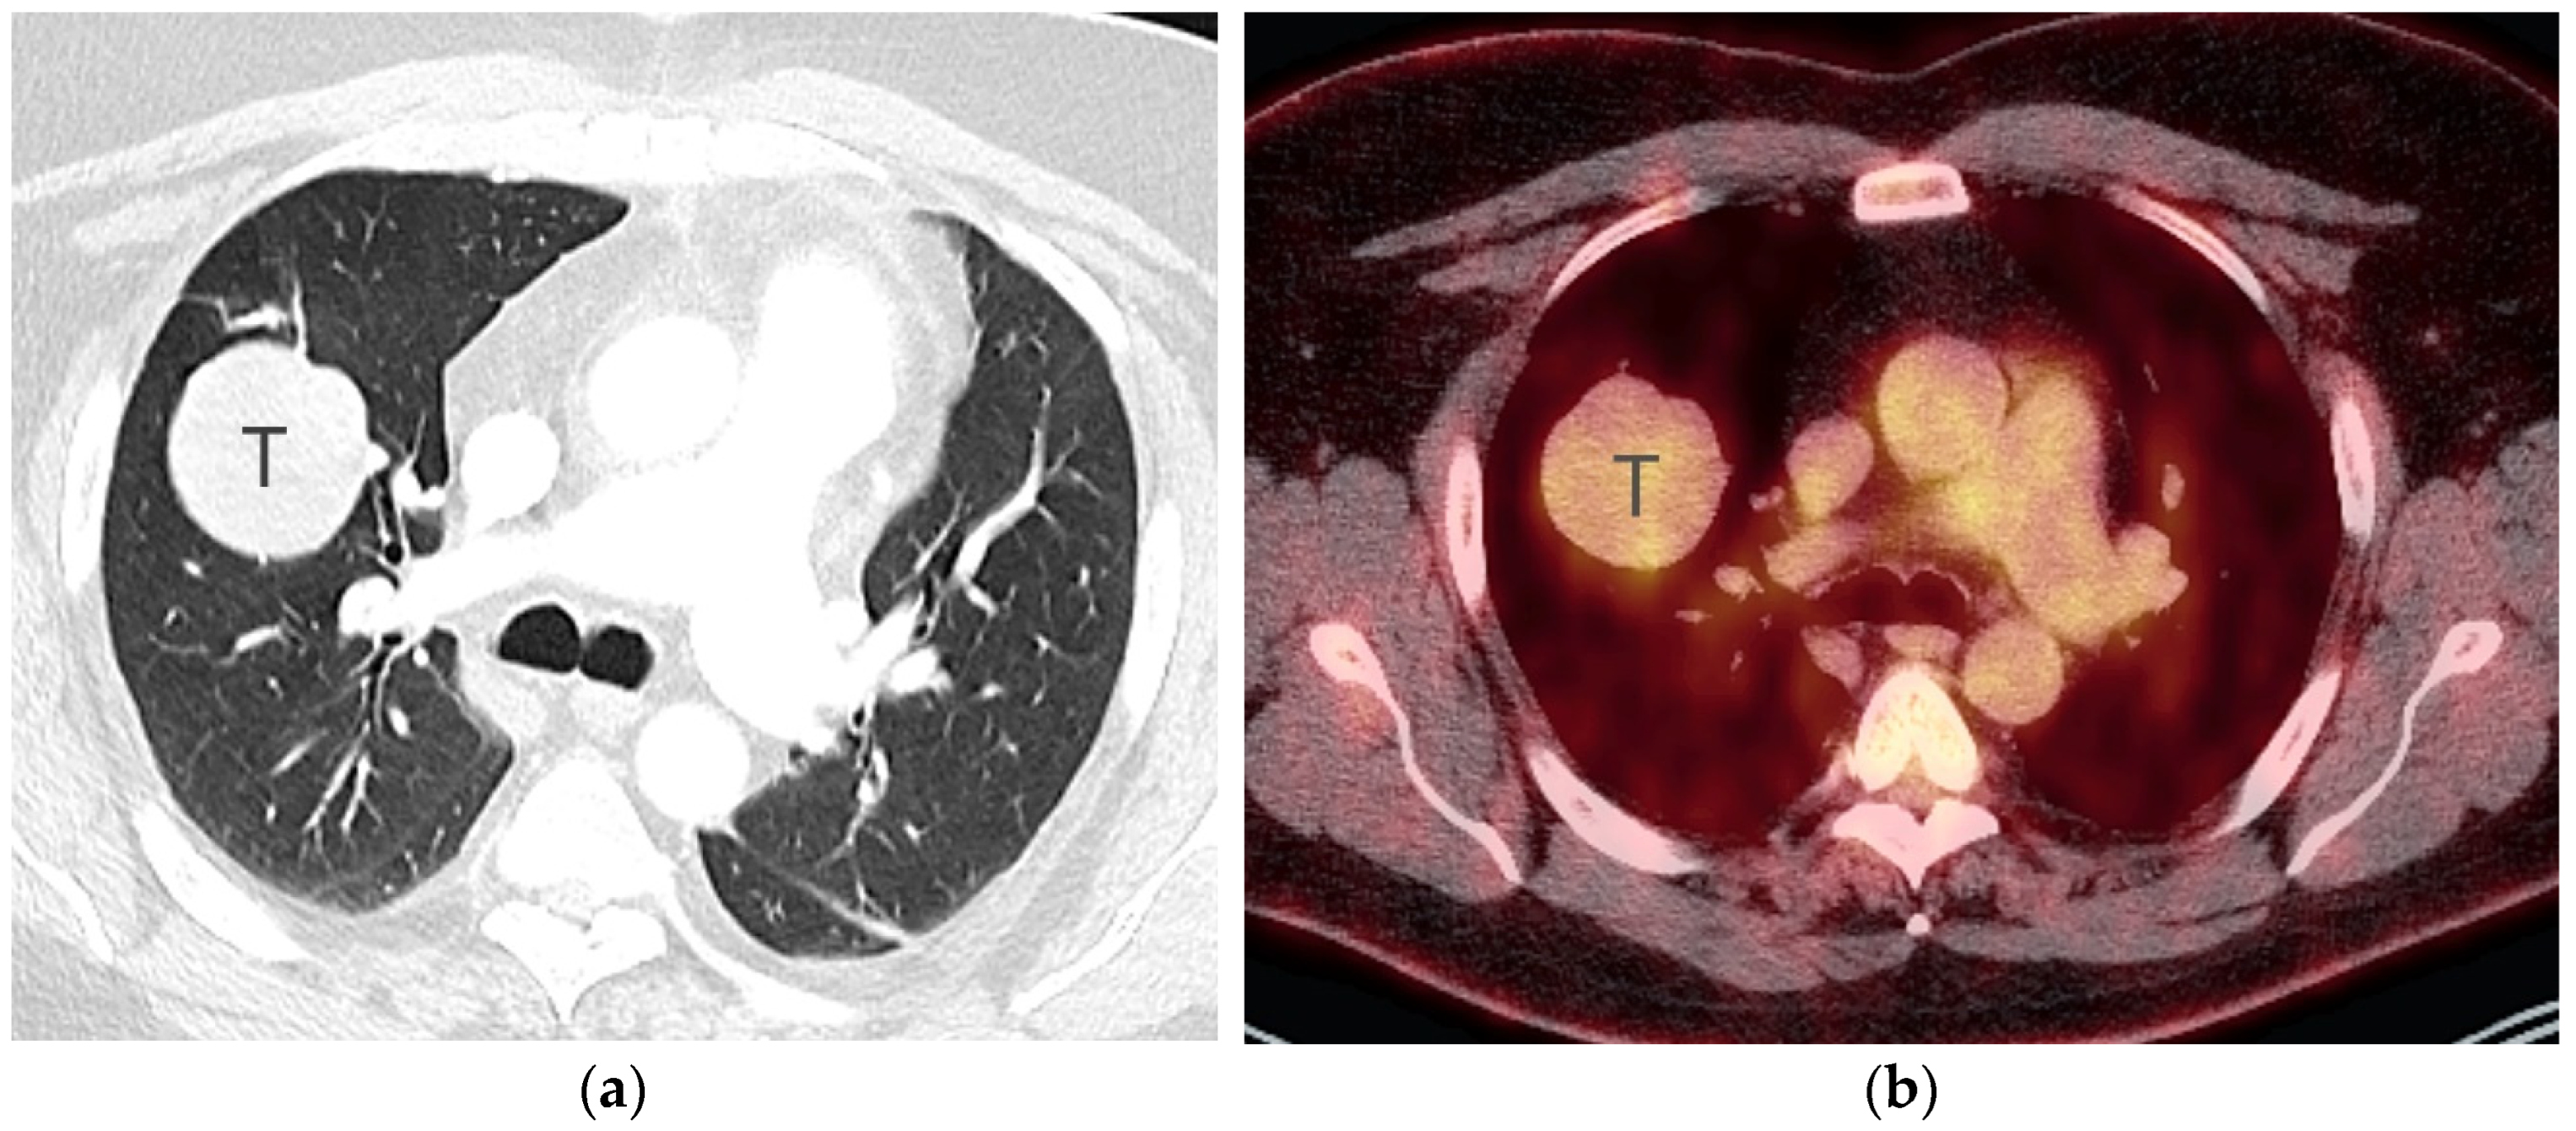

2. T Classification